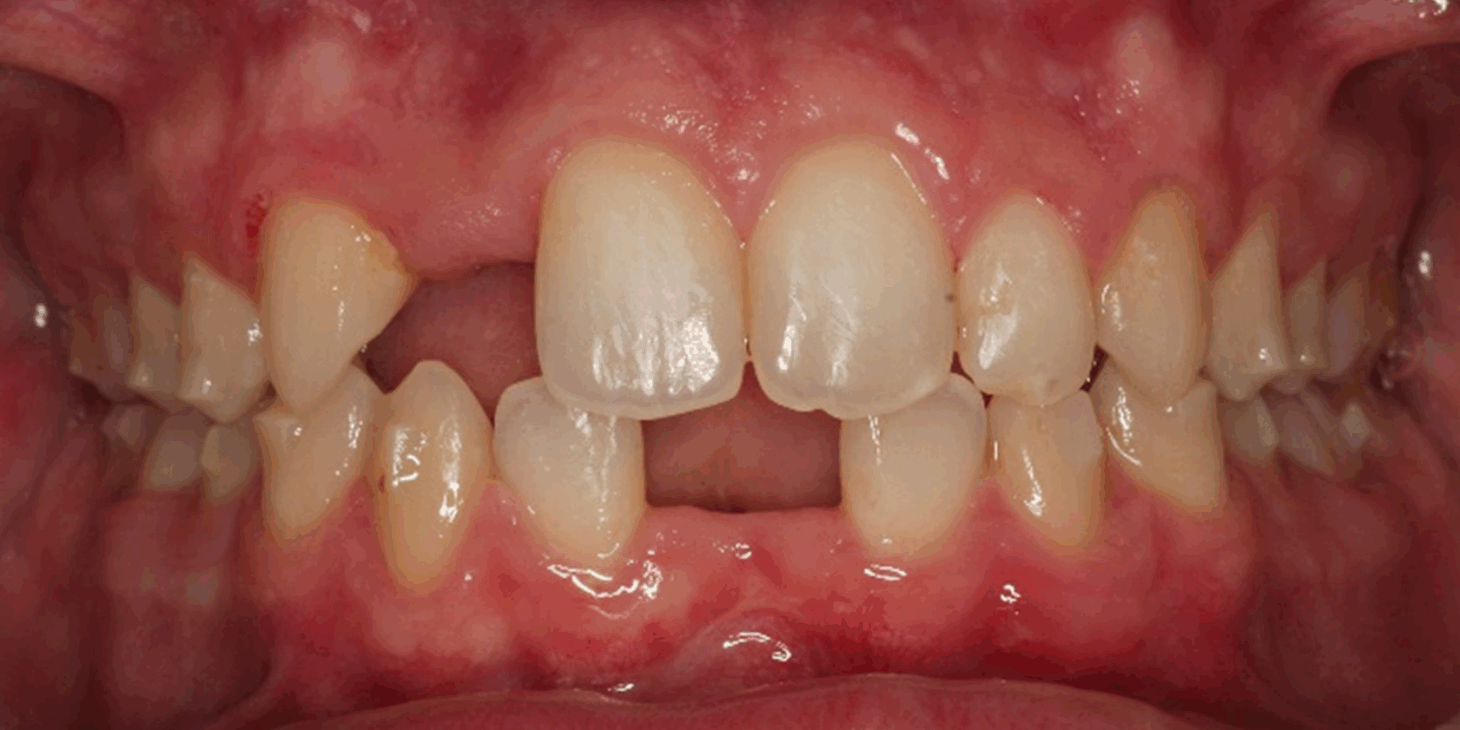

Skeletal Class II due to mandibular retrognathia, proclination of maxillary incisors, narrow arch creating a V-shaped arch, agenesis of 12, 31, 41, hyperdivergent facial pattern, moderate deep bite (2 mm), increased overjet (9 mm), asymmetric canine and molar Class II due to mandibular deviation to the left, maxillary midline deviation related to agenesis of 12, distal rotation of 35 and 45, and pronounced lower curve of Spee.

Overjet reduced from 9 mm → 4 mm

Clear improvement in labial competence, nasal breathing, and tongue function.

Upper arch: 20 active aligners

Transverse expansion

Derotation with mesial-out of first molars

Space opening for 12 by distalizing 13

Maxillary midline correction